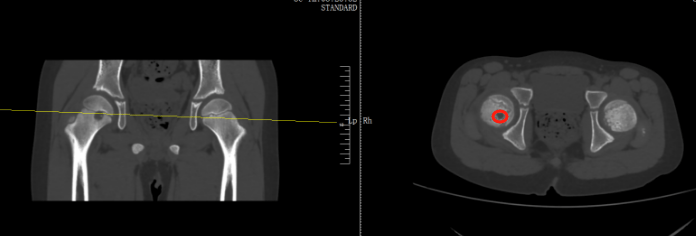

检查后,医生发现,肿瘤直径约有20厘米,基本占满了女孩的右侧屁股,万幸还未出现远处转移,可以通过手术将肿瘤剥离那可恩普拉托姆联vs查英特贺纳比尔 。